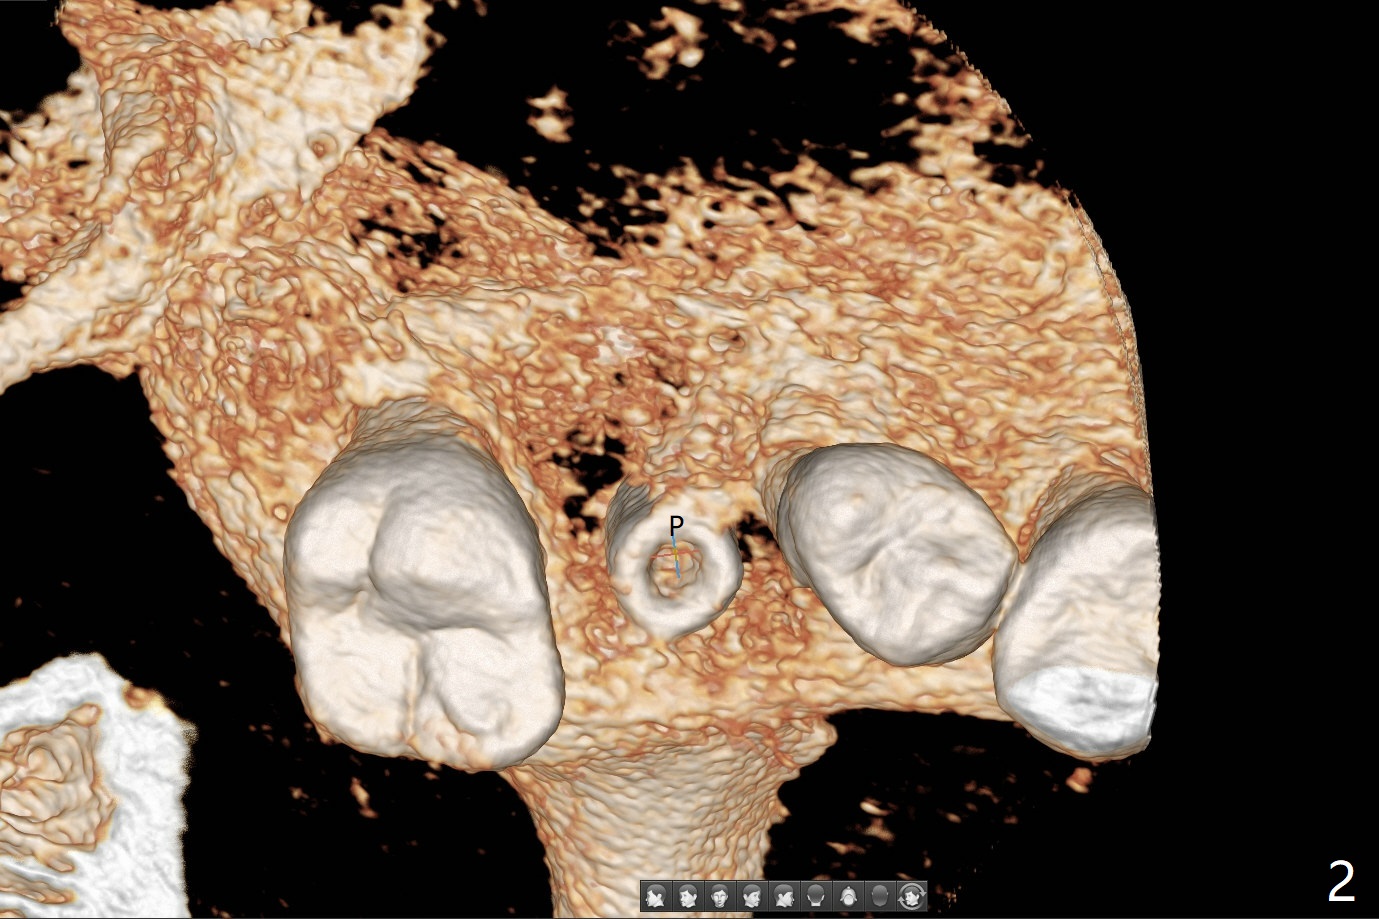

Low bone density is confirmed during osteotomy at #14 (6 months post socket preservation).  Underprep is adopted: after use of 3.5x10 mm drill instead of 4.5x10 mm one, a 4x10 and 4.5x10 mm dummy implant are placed for bone condensation.  When a 5x10 mm definitive implant is placed, it is unable to be placed to the depth.  After use of 4.0x10 mm, the final implant reaches depth ~ 1 mm more than planned.  But there appears no bone palatal to the implant clinically.  Small-field CT is taken.  In fact there is crestal bone palatal to the implant, but in small amount and in low bone density (Fig.1,2).  The implant should have been designed to be placed more buccal (Fig.3 arrow).  The implant also looks to be placed too close the root of the tooth #13, probably related to the rotation of #13 (Fig.4).  Unfortunately the patient does not agree to have limited orthodontics.  After palatal bone graft, GEM Cap is used to close the access with periodontal glue (Fig.5).  Spacer/periodontal dressing should have been used.  The wound heals 8 months postop, but 2-3 palatal threads are exposed with uncover.  After 6 mm profile drill and placement of a 6x4 mm healing abutment, allograft is placed palatal (Fig.6).  Upper Molar Immediate Implant, Trajectory II Shield Next Case of Buccal Defect  SP Xin Wei, DDS, PhD, MS 1st edition 11/19/2019, last revision 09/19/2020